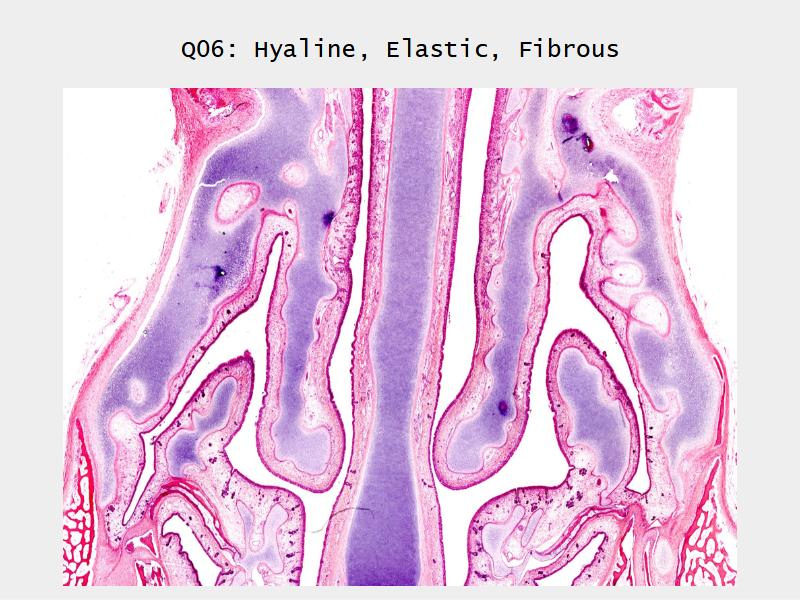

Slides: Respiratory System

- Slide 71: Nostril

Nostril